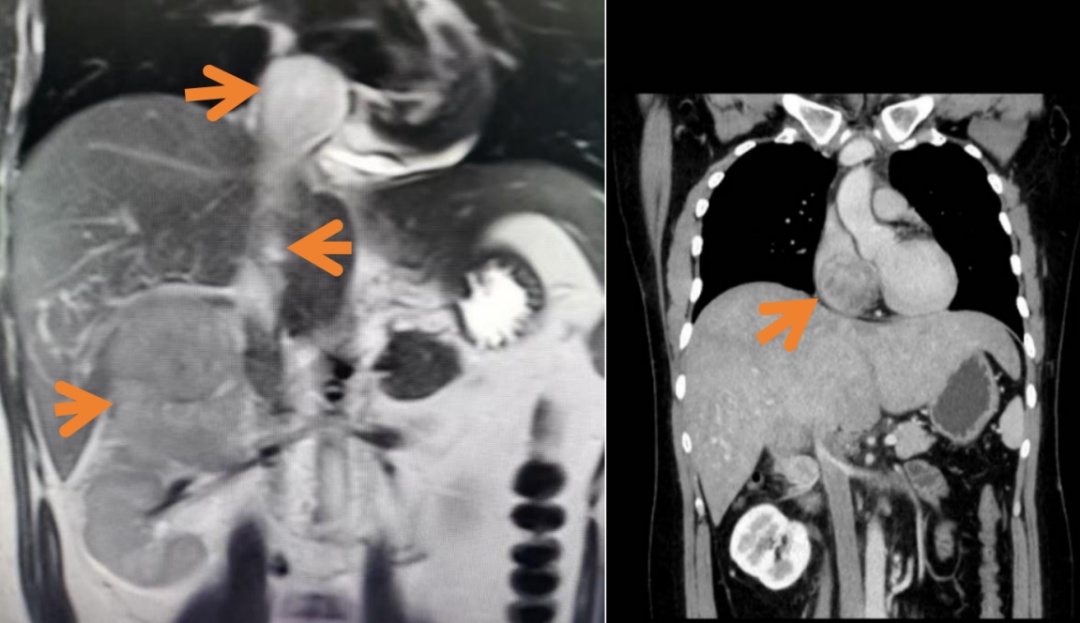

经过一遍遍仔细查找,医生在极其“逼仄”的范围,发现了“元凶”,也就是阿峰右肾上腺紧贴肝脏和右肾的位置,一个接近10公分的巨大肾上腺肿块,压迫在了周围血管、肝脏和肾脏。

右肾上腺皮质癌、下腔静脉癌栓、右心房癌栓

右心房癌栓

遗憾的是,年轻的阿峰属于极少数,在完善了穿刺活检后,他被确诊为“肾上腺皮质恶性肿瘤”(adrenocortical carcinoma, ACC),并且合并心脏、下腔静脉癌栓。这属于恶性肿瘤的一种,发病率极低,但恶性程度高、病情进展快、易局部转移。